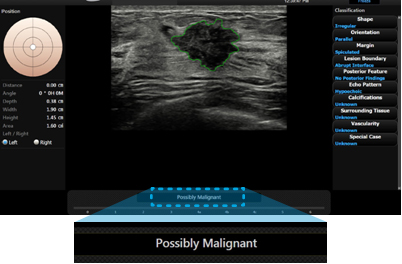

S-Detect™ for Breast

S-Detect™ employs BI-RADS® scores for standardized analysis and classification of suspicious lesions.It provides the characteristics of displayed lesion and recommendation on whether the lesion is malignant by dopting advanced detection algorithm.

With 3 modes included in S-Detect™, users can set the level of sensitivity and specificity for a specific purpose. Such technology assists in a more accurate diagnosis, while reducing the time users spend in repetitive tasks.

* 3 modes : High sensitivity / High accuracy / High specificity